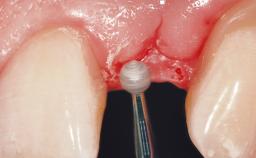

Immediate Placement of an Implant in a Maxillary Right Central Incisor Site

A 30-year-old female patient was referred to the office for the treatment of tooth 11. Her chief concern at the initial visit was to inquire, “Why is my tooth pink?” Upon clinical examination, it was determined that tooth 11 had a previous history of trauma and that the clinical crown had become noticeably pink in color as a result of internal resorption. This diagnosis was confirmed radiographically, indicating a large radiolucency involving the central and distal portions of the clinical crown. It was determined that restoration of this tooth was not possible, and that extraction was indicated. The presence of a mid-line diastema, which the patient wanted to reproduce, directed the treatment plan for tooth replacement utilizing a dental implant.

Soft Tissue Contour and Volume Ideal